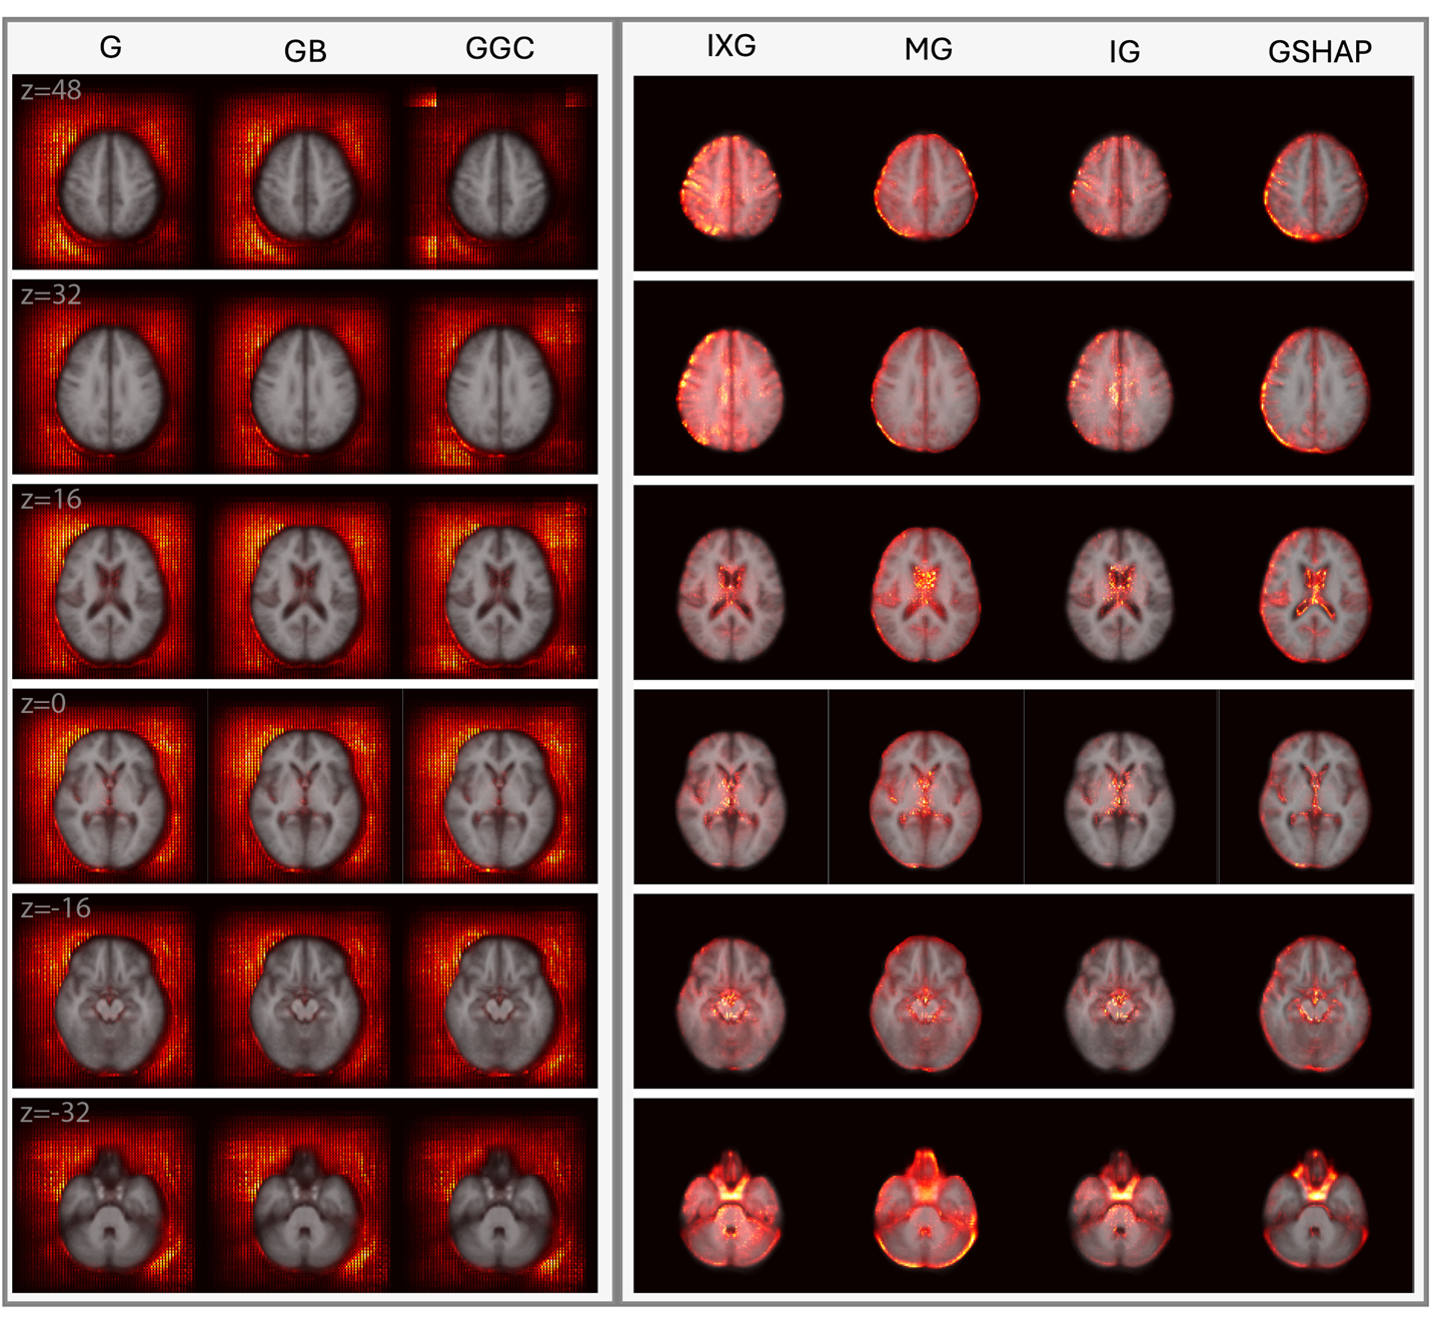

Previously, I received a Bachelor’s in Computer Science from the University of Southern California. At USC, I worked on interpretable neuroimage deep learning advised by Prof. Andrei Irimia. I also spent two years as an AI/ML Research Intern at NASA Ames working on NLP for air traffic control under Stephen Clarke and Dr. Krishna Kalyanam in the NASA Aeronautics Research Institute.

- [10.2024] My manuscript on saliency methods for neuroimage deep learning was published in the latest issue of the Neuroinformatics journal. Read it here!

Neuroinformatics

Kevin H Guo, Nikhil N Chaudhari, Tamara Jafar, Nahian F Chowdhury, Paul Bogdan, Andrei Irimia, Alzheimer’s Disease Neuroimaging Initiative

Springer Neuroinformatics (Neuroinformatics), 2024.